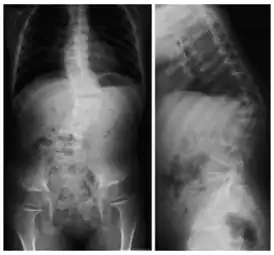

![]() Рентгеновский снимок позвоночника пациента с кифосколиозом. На проекциях хорошо видно искривление позвоночного столба вбок (сколиоз) и выпуклостью назад (увеличенный кифоз) | |

Кифосколио́з (греч. kύφο – согнутый, горбатый и греч. σκολιός – кривой, лат. scoliōsis) – патологическое искривление позвоночника в сагиттальной и фронтальной плоскости, то есть одновременно в переднезаднем и боковом направлениях. Кифосколиоз сочетает в себе два заболевания – кифоз и сколиоз. Может быть как врождённым, так и приобретённым.

При подозрении на кифосколиотическое искривление позвоночника необходимо пройти обследование у ортопеда. Диагноз «кифосколиоз» ставится на основании внешних признаков и данных инструментальных методов исследования. При внешнем осмотре выявляется усиленная сутулость (на поздних стадиях заболевания – горб), сужение грудной клетки и слабость мышц брюшного пресса, различная высота плеч, лопаток, асимметрия таза, видимое отклонение позвоночника от срединной линии при наклоне вперед и расширение межрёберных промежутков на противоположной боковому искривлению стороне. С помощью пальпации спины, шеи и конечностей производится оценка кожной чувствительности, сухожильных рефлексов и симметричности силы мышц. При выявлении неврологических нарушений обязательна консультация невролога. Из инструментальных методов обследования при подозрении на кифосколиоз в первую очередь проводится рентгенография позвоночника, позволяющая определить угол деформации. Наряду с двумя основными проекциями снимки могут выполняться в специальных положениях (лежа, стоя, при растягивании позвоночника). Для уточнения диагноза могут быть назначены методы послойного исследования позвоночника: магнитно-резонансная томография и компьютерная томография. При наличии симптомов нарушения работы внутренних органов может потребоваться дополнительная диагностика и консультация профильных специалистов: кардиолога, пульмонолога, гастроэнтеролога, уролога.